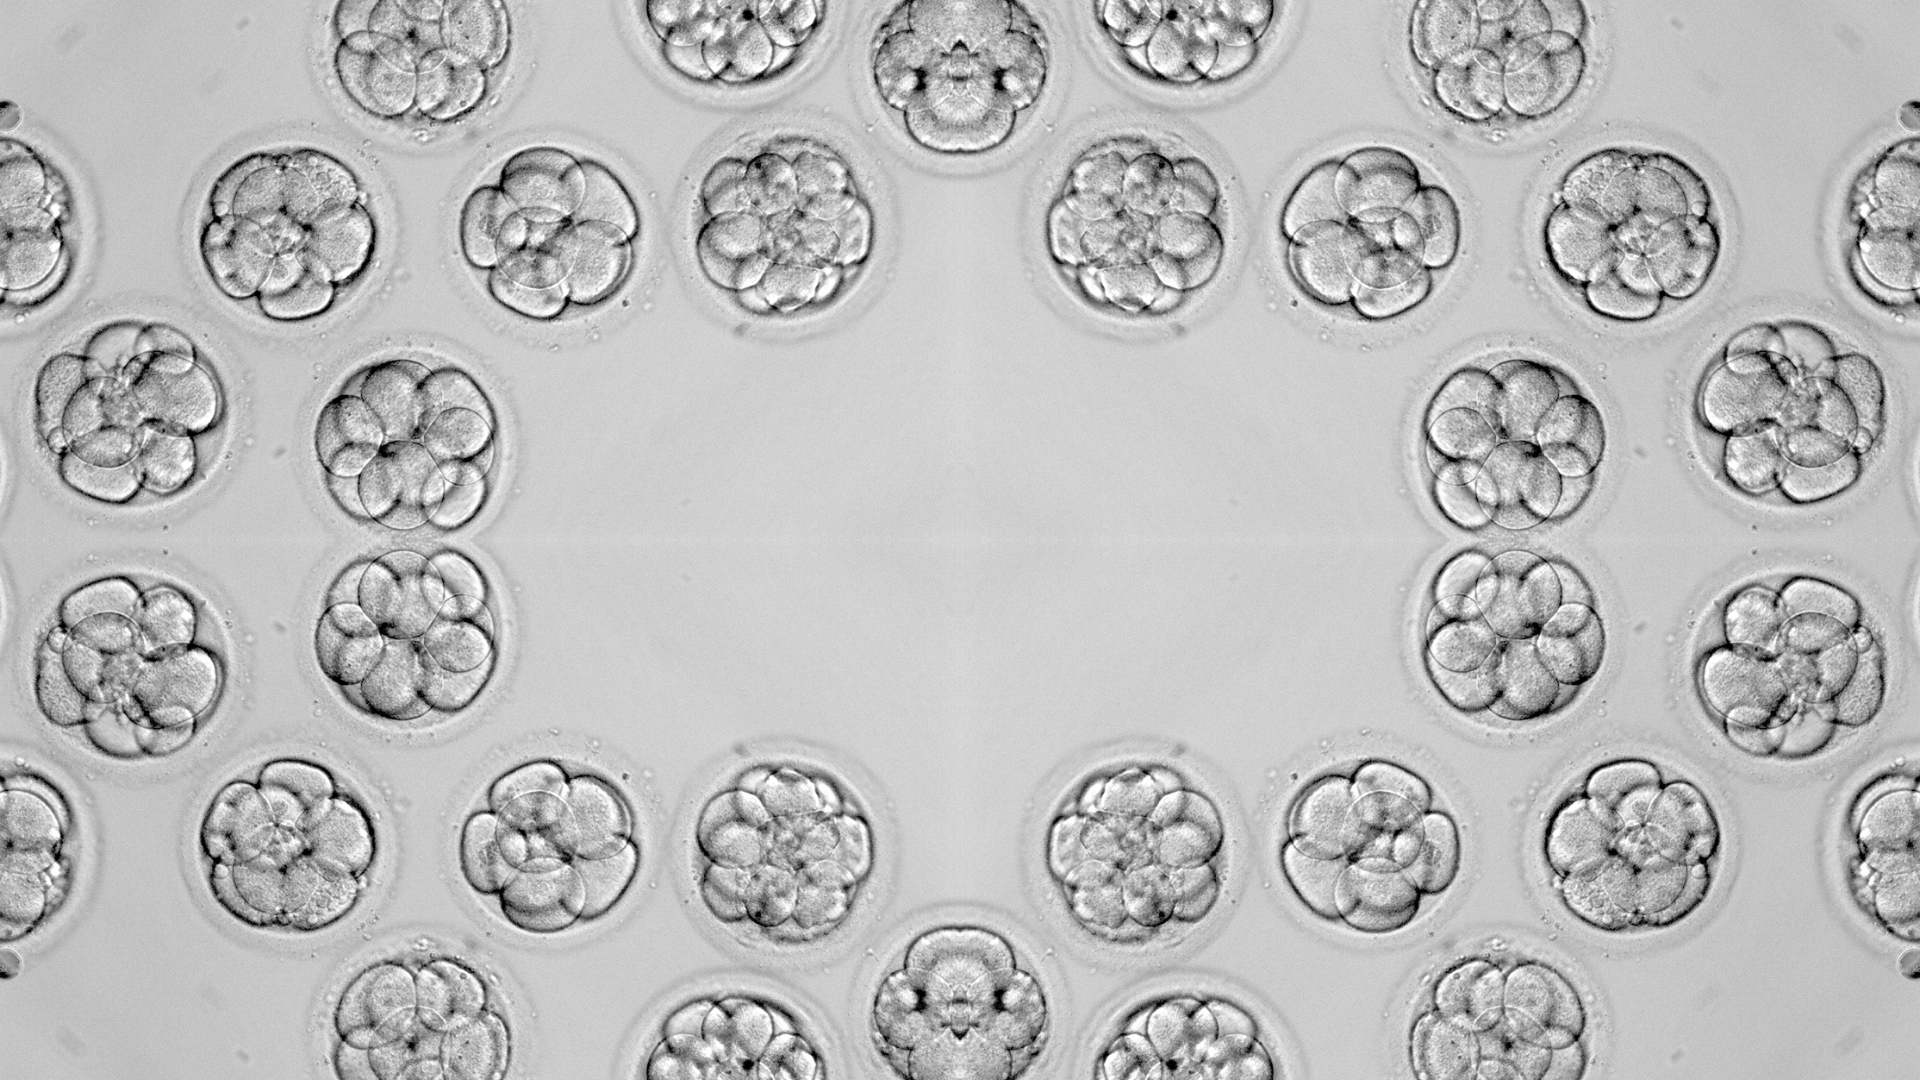

Đánh giá và chọn phôi chuyển: Phôi được phân loại theo tiêu chuẩn của Hiệp hội Y học sinh sản Hoa Kỳ (ASRM) dựa trên số lượng tế bào, tốc độ phân chia và mức độ đồng đều. Hai hình thức cấy phôi thường được áp dụng: chuyển phôi tươi (thực hiện ngay sau khi trứng được thụ tinh và phát triển đến ngày 3 hoặc ngày 5) và chuyển phôi trữ đông: phôi được trữ lạnh và chuyển vào một chu kỳ đã chuẩn bị nội mạc tối ưu hơn.

Chất lượng phôi: Chất lượng phôi là yếu tố then chốt ảnh hưởng đến khả năng phát triển thành thai khỏe mạnh. Phôi ngày 5 (phôi nang) thường có tỷ lệ thành công cao hơn phôi ngày 3. Tiêu chuẩn đánh giá dựa trên hình dạng, tốc độ phát triển và tính toàn vẹn của tế bào.